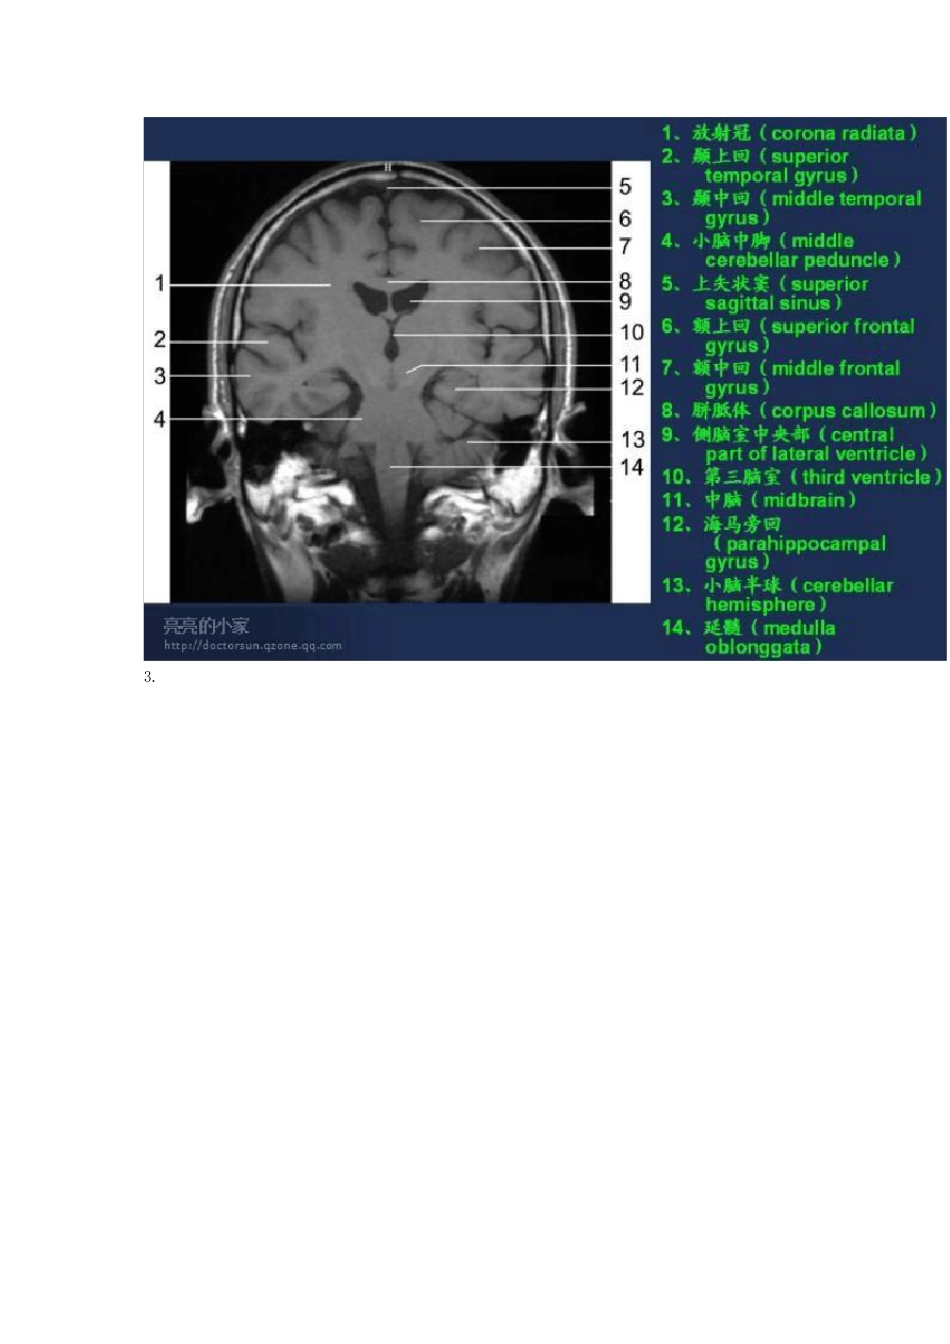

头颅MRI(磁共振成像)断层图谱